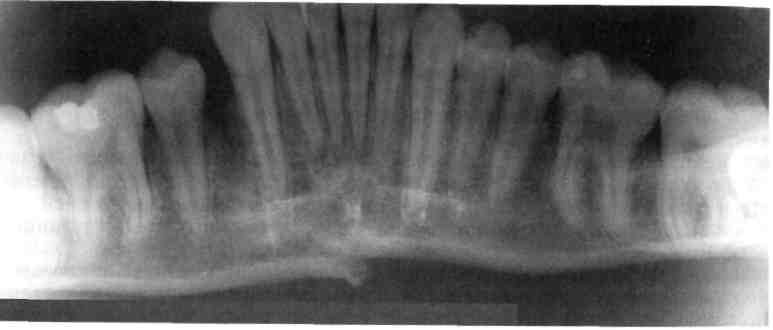

Рис. 10.19. Поднадкостничный перелом тела нижней челюсти без смещения фраг­ментов. Линия перелома проходит через зачатки клыков.

венечного отростка бывают редко (см. рис. 10.17). Если переломы происходят по типу «зеленой ветки» (рис. 10.19), поднадкостнично или бывают не­полными, типичные признаки пе­релома отсутствуют. Интенсивно нарастающий отек, гематомы, осо­бенно в области дна рта, нарушают артикуляцию, вызывают слюноте­чение, боль. Установить же типич­ные признаки перелома нижней че­люсти (нарушения прикуса, функ­ции, подвижность отломков) слож­но. При осмотре ребенка требуют­ся очень бережное отношение, тща-

тельные выбор и проведение обез­боливания.

При одинарных полных перело­мах тела нижней челюсти смещение отломков обусловлено его направле­нием, функцией жевательных мышц и размером фрагментов (рис. 10.20). Выраженность смещения увеличи­вается по мере удаления линии пе­релома от центральных резцов. На­рушение целости слизистой оболоч­ки, подвижность или полный вывих зубов в линии перелома наблюдают­ся почти во всех случаях.